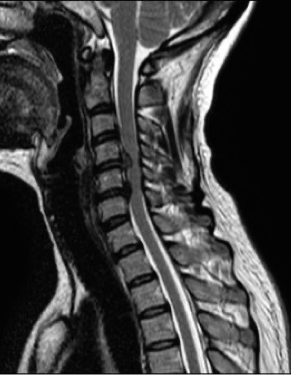

Injury to spinal cord (cervical, thoracic) high spinal anaesthesia.

Neurogenic shock

- Loss of sympathetic tone due to cord injury

- Hypotension, warm well perfused limbs, diminished/absent motor function

- Bradycardia